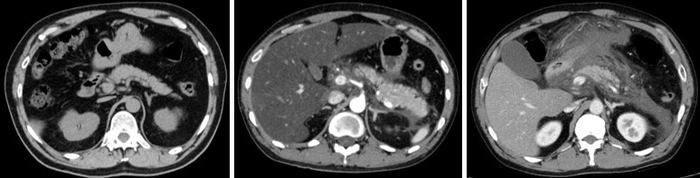

まず、急性膵炎モデルマウスを用いて、LRRK2の機能を亢進あるいは低下させた場合に、症状がどのように変化するかを検証しました。その結果、LRRK2の活性化により膵炎が重症化し、逆に、LRRK2の機能を低下させると膵炎が軽症化することがわかりました。

さらに、LRRK2の機能を活性化させた膵炎モデルマウスを用いて、腸管内の細菌・真菌をそれぞれ除去した場合の症状を比較したところ、真菌を除去した場合にのみ重症化が顕著に抑制されることが分かりました。この結果から、膵臓が真菌に感染した場合、特に急性膵炎が重症化する可能性が示唆されました。また、LRRK2が活性化しているモデルマウスの膵臓では、細菌ではなく真菌の成分に反応して免疫反応が起こることも明らかになりました。

研究グループは、自分たちの先行研究をもとに、セルレイン※4 という分子をマウスに繰り返し投与して急性膵炎を誘導しました。この急性膵炎モデルマウスに対して、まずはLRRK2を特異的に抑制する阻害薬を投与すると、膵炎を引き起こす炎症性サイトカイン※5 反応が低下し、急性膵炎が軽症化することが分かりました。また、全身の細胞にLRRK2が強く発現し、LRRK2の機能が活性化しているLRRK2トランスジェニックマウス(LRRK2 Tgマウス)に膵炎を誘導したところ、阻害薬投与の場合とは逆に、炎症性サイトカイン反応が増加し、急性膵炎が重症化することが判明しました。ここから、LRRK2の機能亢進と低下が、それぞれ膵炎の重症化と軽症化に関与することを発見しました。

さらに、急性膵炎の重症化に、細菌と真菌のどちらがより影響するか検証するため、腸管内の細菌と真菌をそれぞれ抗細菌薬と抗真菌薬で除去し、症状の変化を確認しました。その結果、抗細菌薬による細菌の除去はLRRK2 Tgマウスの膵炎の重症度に影響を与えず、抗真菌薬による真菌の除去により、膵炎は著しく軽症化しました。さらに、重症膵炎を発症したLRRK2 Tgマウスの膵臓のマクロファージ・樹状細胞は、細菌成分ではなく真菌成分に反応し、炎症性サイトカインを多く産生しました。

最後に、腸管の真菌叢の違いにより、LRRK2の機能が変化し、膵炎の重症化に影響しているかどうかを検討しました。次世代シークエンス解析により、野生型マウスとLRRK2 Tgマウスの真菌叢を網羅的に解析した結果、常在真菌叢のレベルでは大きな違いはなく、真菌叢の違いは重症化に影響しない可能性が高いことが明らかになりました。